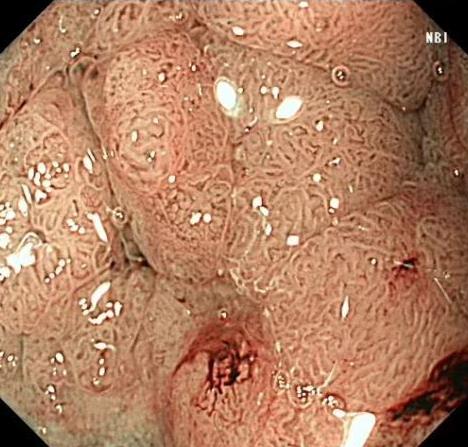

• 色素内镜和窄带成像技术联合放大内镜对早期结直肠癌及癌前病变的诊断价值研究

2026, 32(1):35-41. DOI: 10.12235/E20250020

摘要 (92) HTML (29) PDF 5.33 M (93) 评论 (0) 收藏

摘要:目的 探究色素内镜(CE)和窄带成像技术(NBI)联合放大内镜(ME)对早期结直肠癌及癌前病变的诊断价值研究。方法 选取2023年8月-2024年7月于该院接受检查的疑似早期结直肠癌及癌前病变的患者160例。采用四格表法,分析NBI-ME和CE-ME检测早期结直肠癌及癌前病变的敏感度、特异度和准确度;采用Kappa一致性检验,分析CE-ME和NBI-ME诊断早期结直肠癌及癌前病变与病理检查的一致性。结果 病理结果显示,良性病变52例,癌前病变90例,结直肠癌18例。CE-ME检测结果显示,良性病变43例,癌前病变101例,结直肠癌16例,漏诊率为33.33%;CE-ME诊断早期结直肠癌及癌前病变与病理检查的一致性中度(Kappa = 0.605,P < 0.01),敏感度为66.67%,特异度为97.18%,准确度为93.75%。NBI-ME检查结果显示,良性病变43例,癌前病变100例,结直肠癌17例,漏诊率为16.67%,NBI-ME诊断早期结直肠癌及癌前病变与病理检查的一致性较高(Kappa = 0.714,P < 0.01),敏感度为88.33%,特异度为98.59%,准确度为96.88%。CE-ME与NBI-ME两者联合检查结果显示,良性病变56例,癌前病变86例,结直肠癌18例,漏诊率为5.56%,两者联合诊断早期结直肠癌及癌前病变与病理检查的一致性极高(Kappa = 0.857,P < 0.01),敏感度为94.44%,特异度为99.30%,准确度为98.75%,高于CE-ME和NBI-ME单独检查。结论 CE和NBI联合ME对早期结直肠癌及癌前病变具有较高的诊断价值。值得应用于临床。